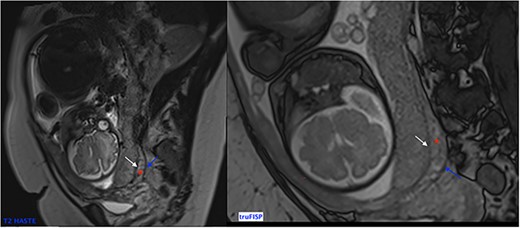

In the case of placenta percreta (like ultrasound), we might have dark intra-placental bands on T2-WI with a heterogenous appearance of the placenta and abnormal disorganized placental vascularity seen as traversing vessels. There’s also focal interruptions of the myometrial wall and the most particular sign in placenta percreta is the tenting of urinary bladder with the involvement of uterine serosa or extra-uterine involvement of adjacent organs like bladder, rectum or abdominal wall [9] (Fig. 5).

Trufisp T2 sagittal-WI of a 44-year-old patient in our department showing the invasion of the urinary bladder.